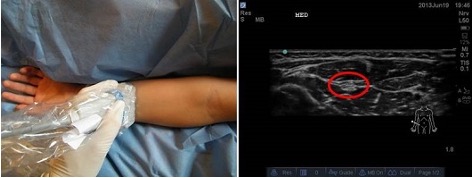

- Identify targets (nerves, fascial planes) – example 1, median nerve to the forearm